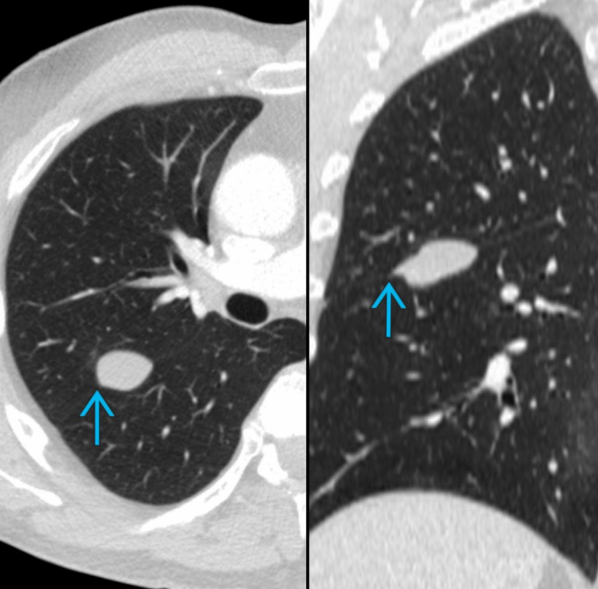

Imagem composta com TC contrastada (CECT) nos planos axial (à esquerda) e coronal (à direita) de um homem de 66 anos com tumor fibroso localizado benigno demonstra uma massa de partes moles na fissura maior direita. Observa-se morfologia em “bico” (beak-like) do tumor ao longo da fissura interlobar adjacente (seta sólida em ciano), achado que sugere origem pleural/fissural da lesão.